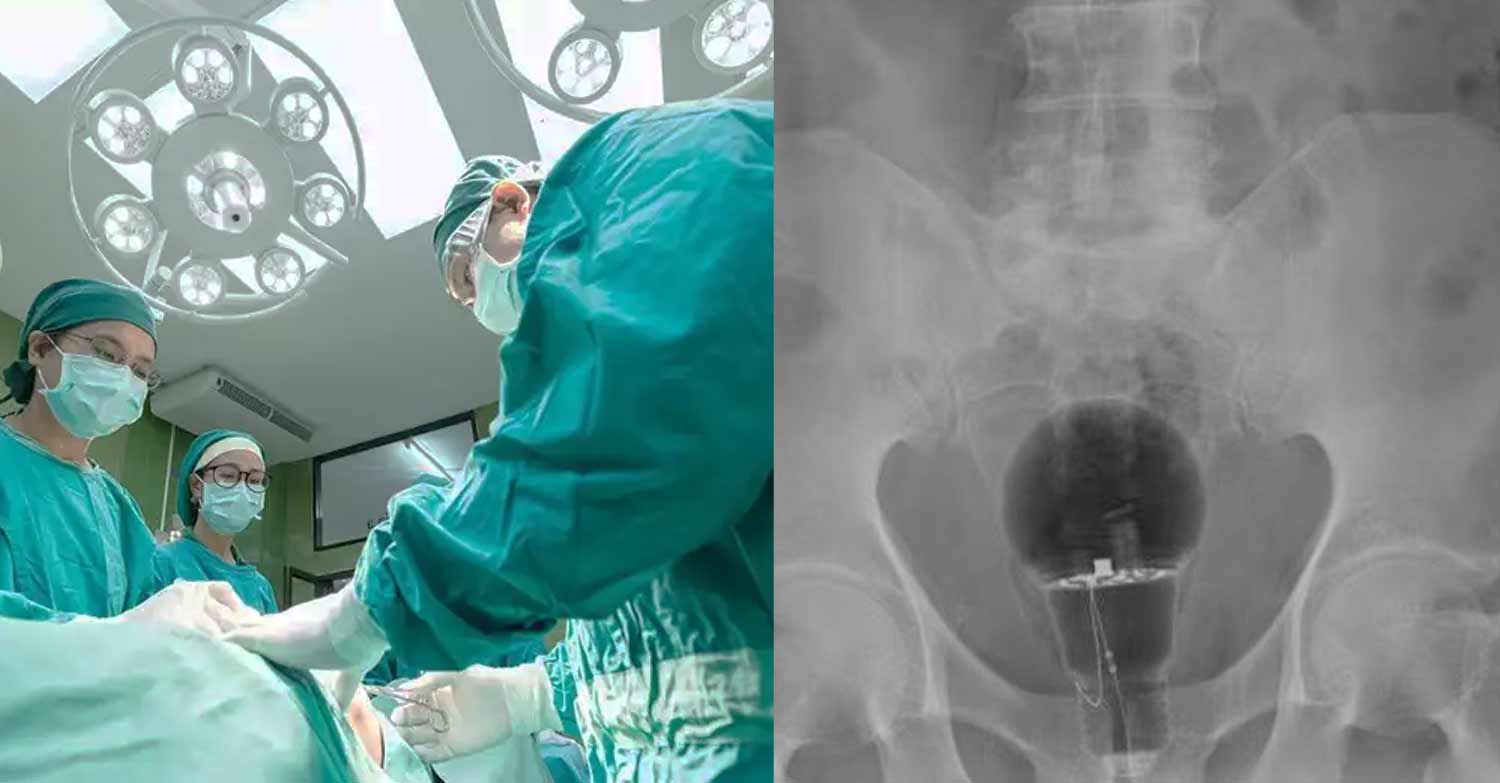

Άναυδοι έμειναν οι γιατροί σε νοσοκομείο της Κολομβίας, όταν διαπίστωσαν πως μια λάμπα βρισκόταν μέσα στον πρωκτό ενός ασθενή, 53 ετών.

Ο ασθενής, ο οποίος δεν έχει κατονομαστεί, πήγε φέτος σε τοπικό νοσοκομείο παραπονούμενος για πόνο στο σημείο. Οι γιατροί δεν είδαν τίποτα κατά τη διάρκεια της φυσικής εξέτασης, αλλά σοκαρίστηκαν όταν μια ακτινογραφία αποκάλυψε μια μεγάλη λάμπα σφηνωμένη, σύμφωνα με τη Daily Mail.

Δεν ήταν σαφές πώς βρέθηκε εκεί ο λαμπτήρας. Δεν ήταν επίσης σαφές πώς αφαιρέθηκε ο λαμπτήρας ή αν το άτομο υπέστη μακροχρόνια βλάβη. Οι γιατροί δήλωσαν ότι ο ασθενής ήταν τυχερός που η λάμπα δεν είχε σπάσει.